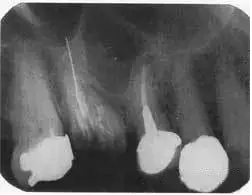

根尖片如图44.2,可观察到什么?

图44.2 上颌第一磨牙的根尖片

第一磨牙大面积龋坏,已行根管充填,但只有一个牙根根管可见根尖,超充根尖接近2mm,颊根不能清楚看见,且未行充填治疗,超充的根管接近于上颌窦,上颌窦向下延伸,位于第一磨牙根与第二前磨牙牙根之间,根尖无暗影。第二前磨牙已行根充治疗,根充看起来刚好位于生理性根尖孔的狭窄处,但根尖有小范围暗影。第一前磨牙冠下方可见龋坏,第二磨牙牙冠可见大范围钉状银汞充填。